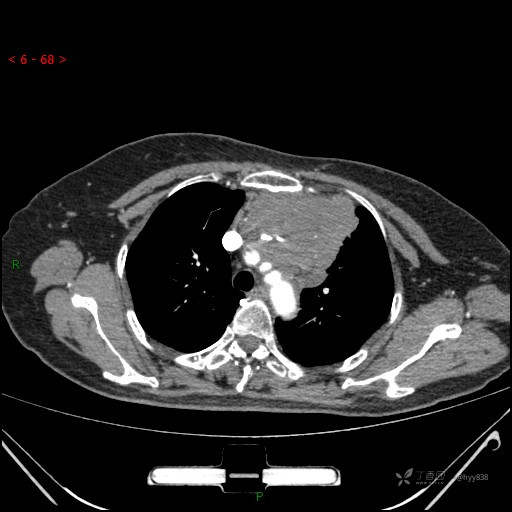

简要病史:患者诉3月余前患新冠肺炎,出现持续性胸闷,活动后可缓解,无胸前区压榨感,无畏寒发热不适,无胸痛咯血、呼吸困难,无恶心、呕吐,无腹痛、腹胀、腹泻等不适,未予以重视,未行特殊处理。患者胸闷持续存在,为进一步诊治,3天前于本院查胸部CT提示前纵膈团块状软组织密度影,肿瘤性病变可能,心包积液,左上肺磨玻璃结节,右下肺增殖灶可能建议进一步检查。门诊以“前纵膈占位” 收入我科。 患者本次起病来精神、食欲、睡眠尚可,大小便正常,体力、体重无明显变化。

辅助检查:CT

临床诊断:纵隔占位

静脉期